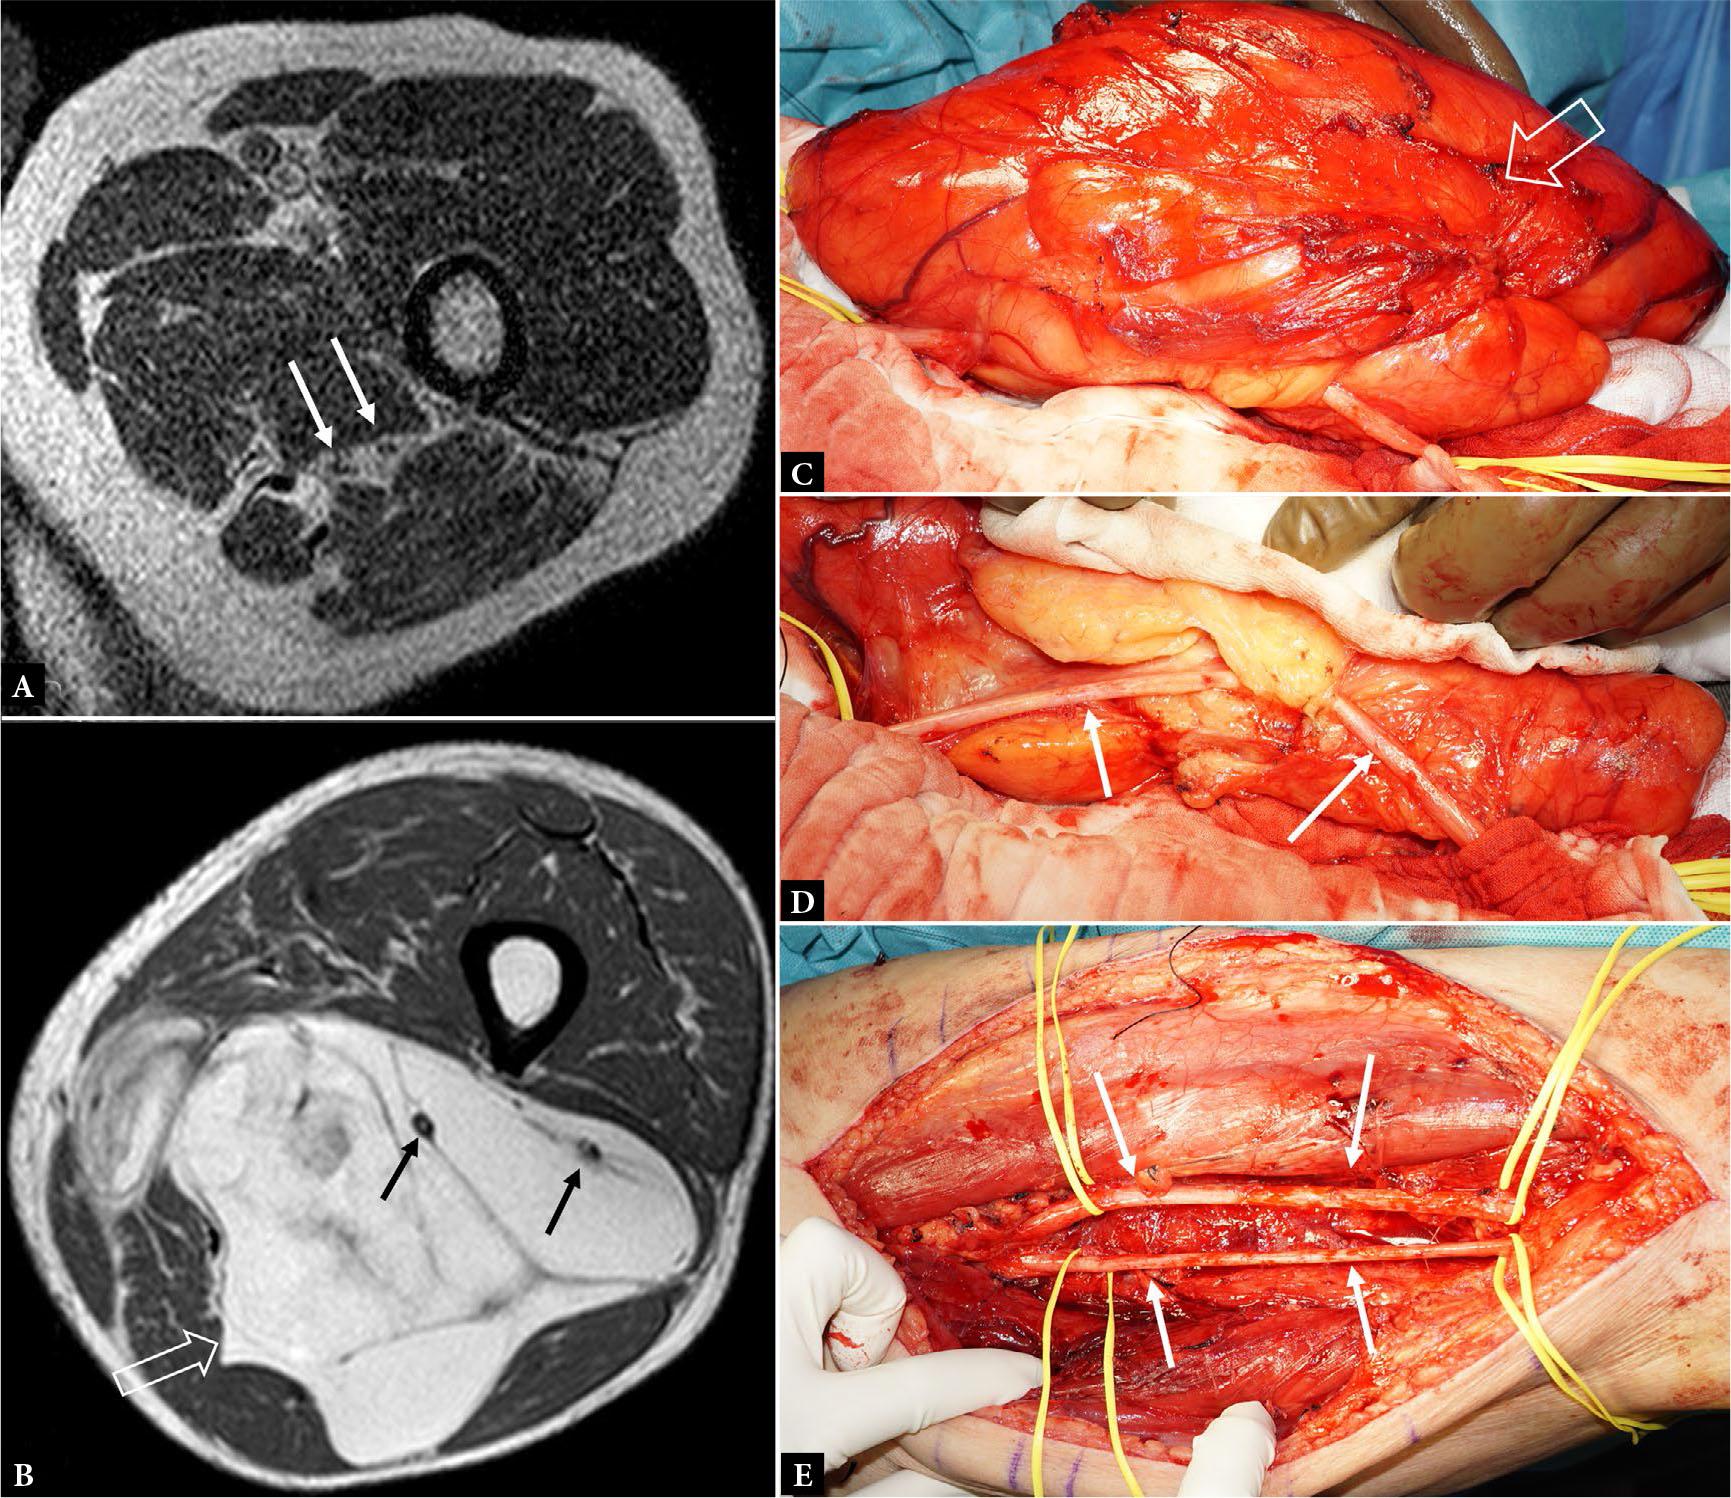

Fig. 20.

78-year-old male with well-differentiated liposarcoma of the thigh. Axial T1W MR image shows A. a high division of the sciatic nerve into the tibial and peroneal nerves (arrows) and B. a large intermuscular liposarcoma (open arrow), between the adductor and hamstring muscle groups, encasing the tibial and peroneal nerves (arrows). C.-E. Clinical photographs of surgically exposed tumor (open arrow) showing the invaginated tibial nerve (arrows) which, for the most part, easily freed from the tumor pseudocapsule. As the tibial nerve was focally tethered in the mid-portion of the tumor, the epineurium in this area was resected. The exposed nerve fibers were not visibly infiltrated by tumor. E. Preserved tibial and peroneal nerves (arrows) after complete tumor resection. Histologically, the tethered small segment of the tibial nerve had epineurial tumor involvement. Three years after resection, the patient has no local recurrence